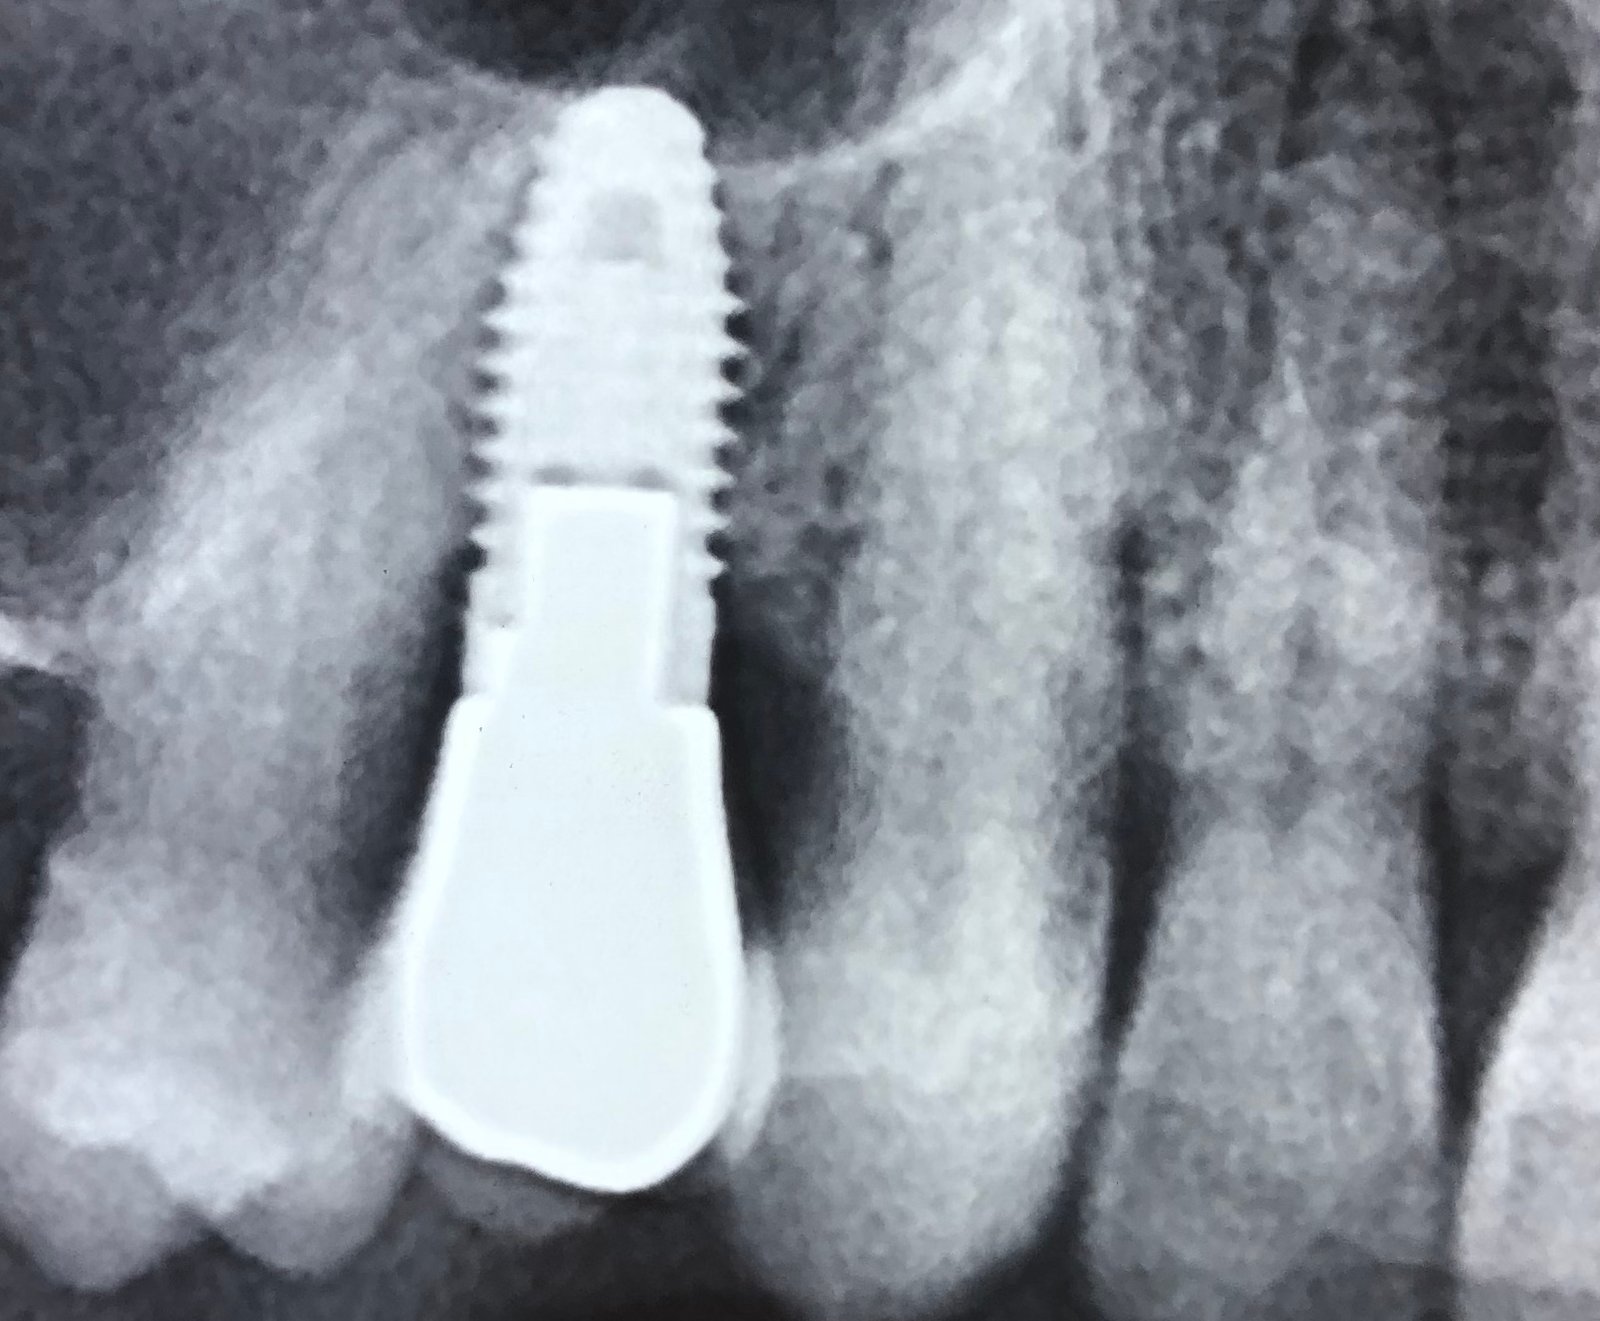

Buenos días: Ruego me ayuden a identificar este implante, tiene conexión interna hexagonal y el tornillo protésico es de 2 mm de diámetro. Muchas gracias.